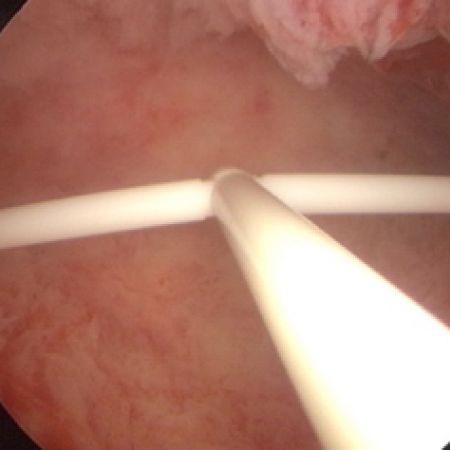

FibroPlant (frameless LNG-IUS): releases 20 mcg of LNG per day and has a lifespan of 5 years. Its major advantage is its compatibility with uterine cavities of every size and shape.

Omega-shaped IUS: This IUS is currently in development. Its Ω-shaped retention arm is resilient and adapts to different cavity widths from very narrow (<1 cm) to wider cavities.

Hybrid- Ω has a resilient retention arm which adapts to different uterine cavity widths.